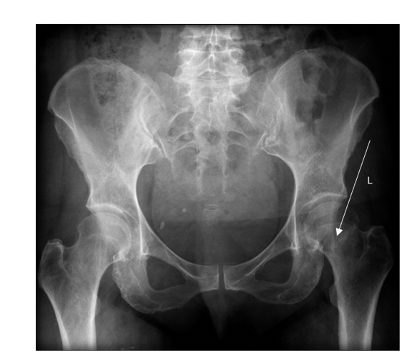

Which direction of hip dislocation is the most common and why?

Posterior because anterior ligaments are stronger

Which structure at risk following hip dislocation

Nerve injury – sciatic nerve is most commonly affected

In what position is affected limb likely to be in posteiror hip dislocation

Flexion, adduction and internal rotation with shortening of the leg.

2 Types dislocaiton of the hips